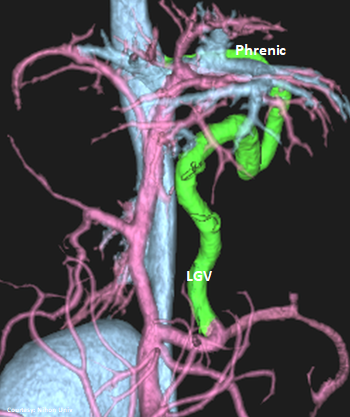

“LGP”

Left Gastro-Phrenic Shunt